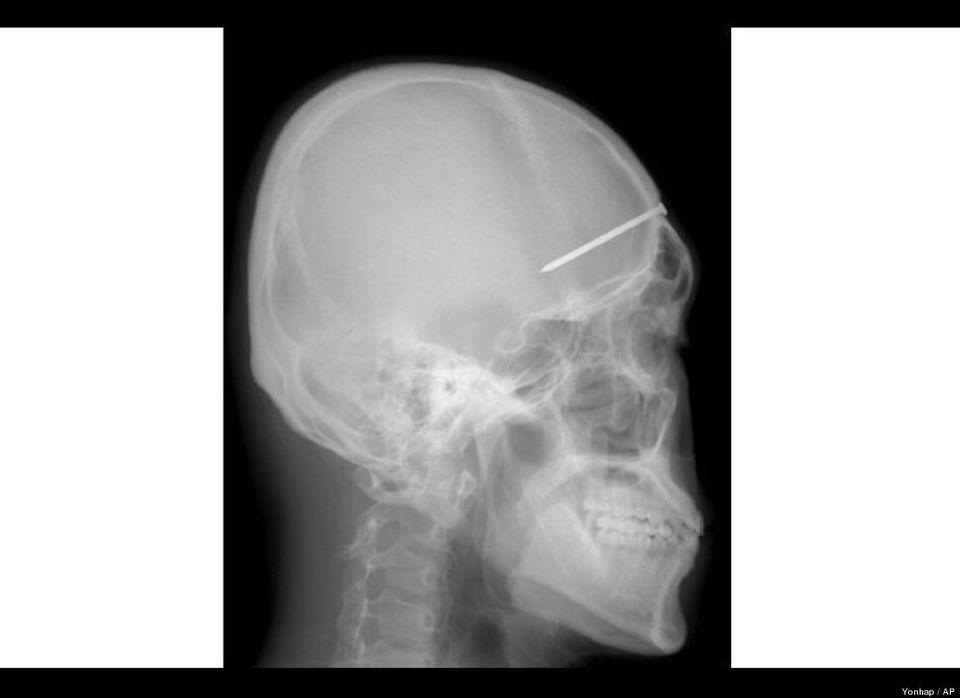

(Dân trí) - Thật khó tin những nạn nhân này đều sống sót và gần như hồi phục hoàn toàn khi các bức ảnh X-quang cho thấy dị vật nằm rất sâu, thậm chí xuyên qua não.

Một khẩu súng bắn đinh đã găm 6 chiếc đinh vào sọ não công nhân xây dựng Isidro Mejia trong một tai nạn vào tháng 4/2004 . May mắn là người công nhân này đã sống sót và phục hồi sau đó.